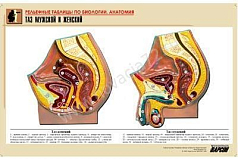

Комплект включает в себя 21 таблицу следующего содержания:

21. Таз мужской и женский.